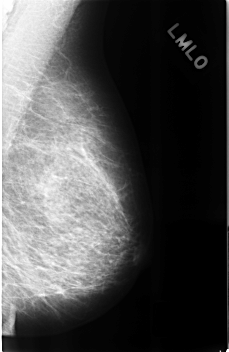

C_0311_1.LEFT_MLO

LEFT_MLO LINES 4568 PIXELS_PER_LINE 2968 BITS_PER_PIXEL 12 RESOLUTION 50 NON_OVERLAY